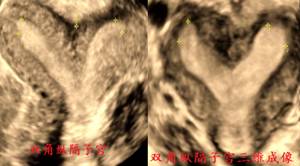

图:双角子宫与纵隔子宫鉴别

图:(左图)完全性子宫纵膈和(右图)不完全子宫纵膈

宫体轮廓无论二维扫查或三维成像均无异常。但由于其内膜腔被纵隔一分为二,二维超声横切时环形肌层切面上出现两团圆形的内膜回声,如猫眼一样,故称“猫眼征”。如为完全纵隔子宫,从宫底至宫颈管的横切面上始终呈现该猫眼征。如为不完全纵隔子宫,从宫底向下直至隔底水平,横切面上均呈现该猫眼征,而低于隔底水平的横切面上仅显示一团内膜。

三维超声上,完全纵隔子宫腔呈兔耳型,整个宫腔被纵隔完全分开。不完全纵隔子宫腔呈Y型,即隔底水平以下为一个宫腔。纵隔深度(两侧宫角的内膜顶点连线中点至纵隔底部的距离)≥10mm。

推荐使用ESHR的定义:宫底浆膜层内陷<子宫前后壁平均厚度50%且宫腔底部下凹深度>宫壁厚度50%,诊断为纵隔;若宫底浆膜层内陷>子宫前后壁平均厚度50%,为双角子宫。